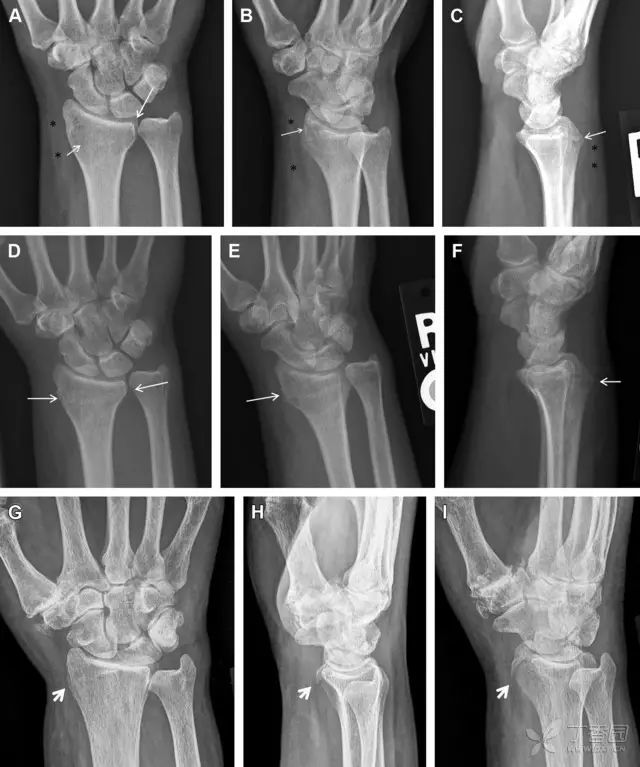

常规进行前后位、侧位、斜位 X 线检查,对于大多数桡骨远端骨折来说不容易漏诊;但是对于无移位的骨折,特别是桡骨茎突骨折,容易漏诊。桡骨茎突骨折是一斜行的骨折,常累及关节面,常发生于轴向应力或直接打击。

图 1 57 岁女性,摔倒后手掌撑地,桡骨茎突压痛。(A~C)前后位、斜位、侧位片示软组织肿胀(*)和发丝样骨折(白色箭头);(D~F)2 周后,前后位、斜位、侧位片示骨折线显明,由于新骨痂沉积而呈现透亮线与硬化线并存;(G~I)另一患者,桡骨茎突骨折在前后位及侧位片上显示不明显,而在斜位片显示更清楚

舟状骨骨折 60%~70% 发生于腰部,15% 发生于近极, 10% 发生于远极, 8% 发生于远端关节面。除了常规的前后位、侧位、斜位片外,还需要拍专门的舟状骨位片(腕关节尺偏,以舟状骨为中心的腕关节前后位片),特别是鼻烟壶有压痛时。

图 2 舟状骨骨折 (A、B)第 1 例患者,舟状骨远极关节内骨折(白色箭头),斜位片显示较清楚(B);(C、D)第 2 例患者,舟状骨腰部骨折(虚线箭头),斜位片显示较清楚(D);(E~H)第 3 例患者,舟状骨近极骨折,常规 X 线片均未看到骨折,而在舟状骨位片上才能见到骨折(虚线圆)

掌板是掌指关节和指间关节关节囊掌侧的纤维结构,防止关节过伸。掌板的远端部是增厚的纤维软骨,附着于指骨掌侧基底部,而其两侧与侧副韧带的纤维融合。掌板骨折多发生于过伸损伤,为撕脱性骨折。

图 3 掌板骨折(A~C)小指前后位、斜位、侧位片,由于骨折的部位及特点,在前后位片上通常难以发现骨折;放大后的斜位(D)、侧位(E)可见一骨碎片(白色箭头)

腕掌关节骨折脱位为高能量损伤,常伴有神经损伤。腕掌关节组成骨多,侧位片上重叠遮挡多,骨折不易发现,容易漏诊。在前后位片上,关节面不平滑、关节间隙不对称、关节皮质破坏、关节面重叠常提示腕掌关节骨折脱位。特别是第 4、5 腕掌关节脱位,在前后位片上不容易发现;该损伤不稳定,也称为「变异型拳击手损伤/骨折」。

图 4 第 4、5 腕掌关节骨折脱位。(A)正常腕掌关节,关节面平衡起伏、平行;前后位(B)、斜位(C)、侧位(D),第 5 掌骨近端附近软组织肿胀(白色箭头),冠状面关节面重叠,背侧撞击剪切应力致钩状骨骨折(*),在前后位及斜位片上可见双密度影。第 4 掌骨底部可见微小骨折碎片(D,虚线箭头),第 4、5 掌骨掌侧成角。(E~G)变异型拳击手损伤:第 4、5 掌骨背侧脱位而未见骨折(E,虚线方框),钩状骨有骨折小碎片(F,短虚线箭头),第 4 掌骨基底部关节内骨折(G,长虚线箭头)

钩状骨骨折可发生于体部和钩部,钩部骨折更多见,可合并有第 4、5 腕掌关节脱位。受伤机制由直接暴力或腕横韧带撕脱伤所致。骨折征象包括钩部无显示、骨皮质边缘模糊、硬化或双密度影等。常规的正侧位常无法明确诊断,需要加拍腕管位,可清晰显示其钩部。

图 5 打高尔夫球后腕部急性疼痛。常规腕关节 X 线片正常(X)。腕管位片(B)隐约可见钩部横行骨折(虚线箭头),CT 检查(C、D)进一步明确了诊断

三角骨骨折是除舟状骨骨折外腕关节常见的骨折之一。其背侧是背侧桡腕韧带的附着点,因此背侧骨折更常见。常规正侧位片基本可明确诊断。背侧骨折可在侧位片上看到一小骨块。

图 6 三角骨骨折。(A)前后位片骨折不明显,(B)仅在侧位片上见一小骨块(短箭头),伴有软组织肿胀(长箭头)。

月骨周围脱位和月骨周围骨折脱位常发生于摔倒后手掌撑地,由过伸、轴向暴力所致。所谓的「脆弱区」包括桡骨茎突、大多角骨、舟状骨、头状骨近端、钩状骨近端、三角骨的月骨缘、尺骨茎突。

图 7 经舟状骨骨折月骨周围脱位(腕关节前后位、斜位、侧位)。(A,B)前后位、斜位示月骨腰部骨折(黑箭头),第 1、2 腕弧中断,舟状骨近极(*)仍在原位,而远极(虚线)背侧脱位